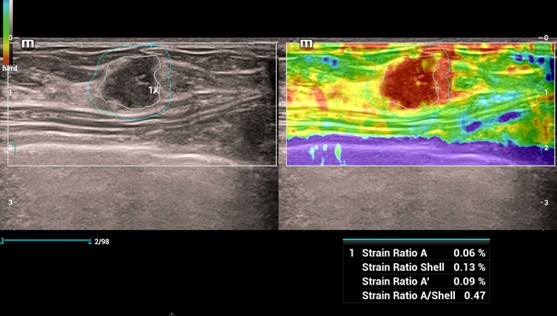

Strain Elastography - Natural Touch Elastografia

Natural Touch Elastografia, Strain Elastografia

HiFR STE Elastography: Kompletná a výkonná elastografia. Shear Wave Elastografia (HiFR STE, STQ). Strain - Natural Touch Elastografia (NTE). Vysoká citlivosť, penetrácia a presnosť. Unikátna “shell” analýza hodnotiaca infiltráciu tumoru do okolia. Automatické ohraničenie ložiska a shear wave kvantifikácia tuhosti tkaniva. Presné posúdenie tuhosti tkaniva pomôže v diagnostickom odlíšení malígneho a benígneho nálezu.

Natural Touch Elastography

HiFR STE Elastography: Kompletná a výkonná elastografia. Shear Wave Elastografia (HiFR STE, STQ). Strain - Natural Touch Elastografia (NTE). Vysoká citlivosť, penetrácia a presnosť. Unikátna “shell” analýza hodnotiaca infiltráciu tumoru do okolia. Automatické ohraničenie ložiska a shear wave kvantifikácia tuhosti tkaniva. Presné posúdenie tuhosti tkaniva pomôže v diagnostickom odlíšení malígneho a benígneho nálezu.

Natural Touch Elastography

Strain Elastography - Natural Touch Elastografia